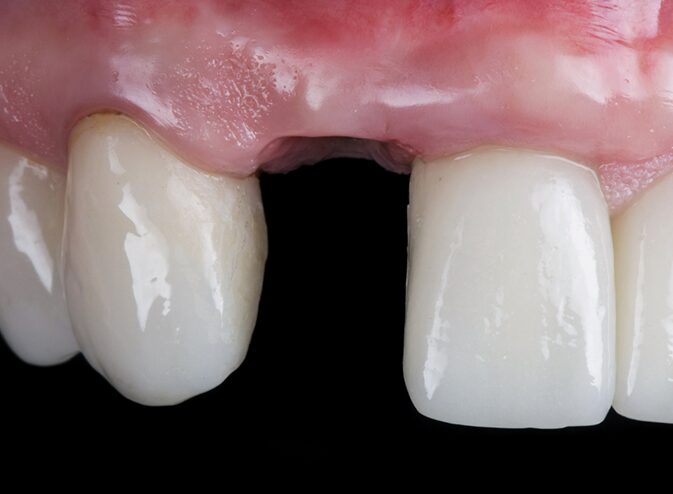

• Repositioning and stabilizing a knocked-out tooth

• Repair using bonding, crowns, or splints